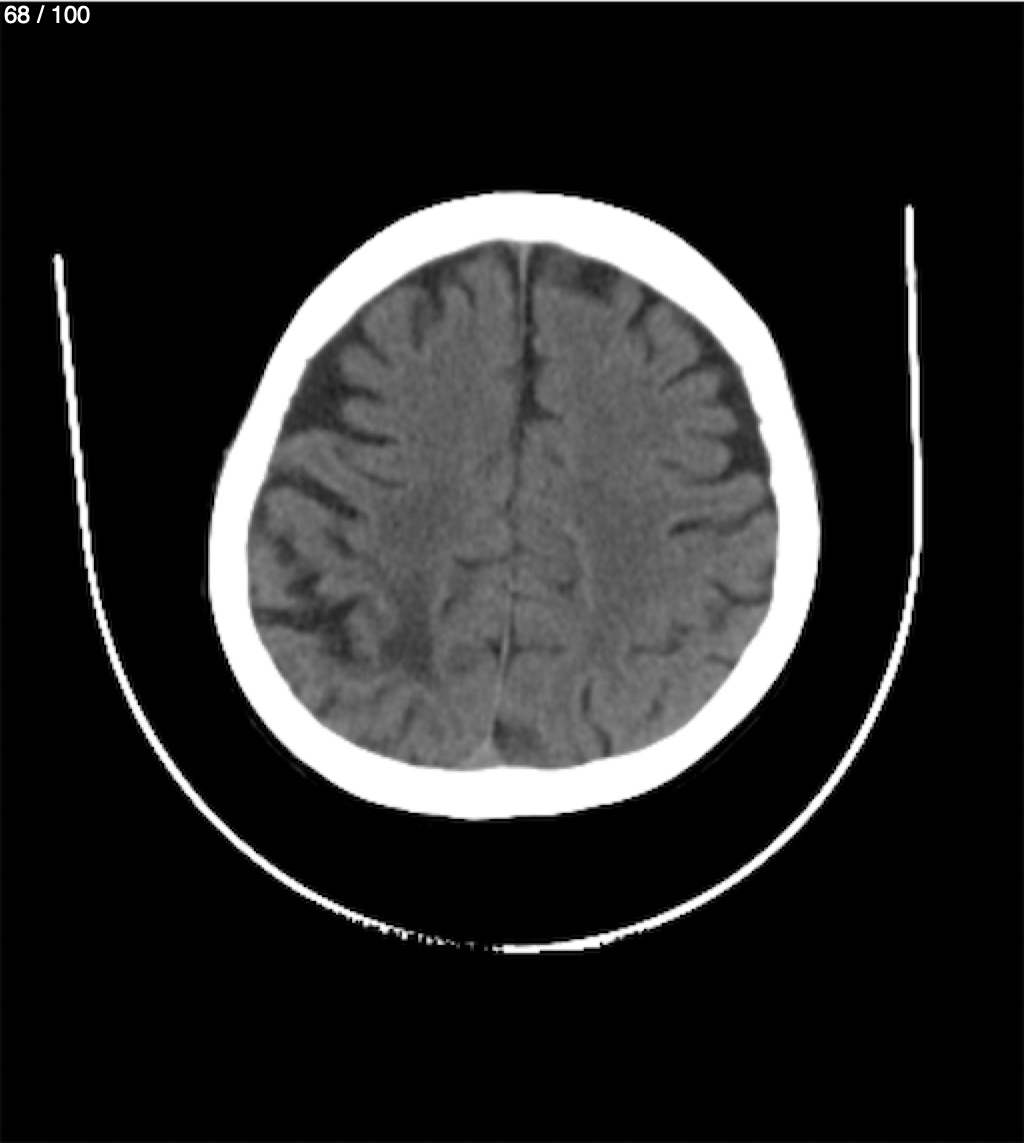

Catarino Perez Escobar 85A - T.C Craneo